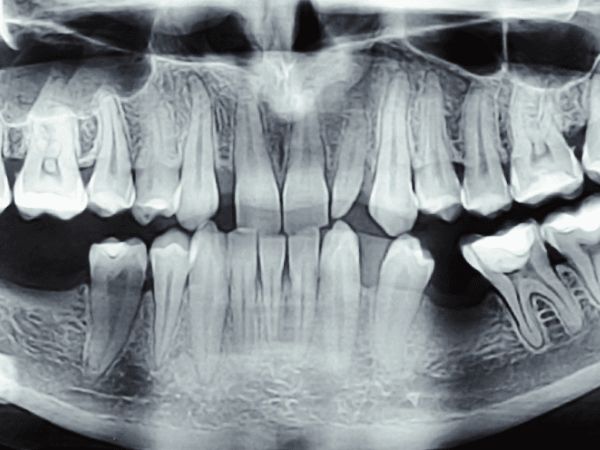

We use state-of-the-art digital radiography and cone beam computed tomography (CBCT) to produce detailed, high-resolution images of teeth, bone, nerves, and surrounding structures — instantly and with up to 90% less radiation than traditional film X-rays. Digital images are displayed chairside in seconds, allowing your dentist to discuss findings with you in real time.

Our 3D CBCT scanner provides a full volumetric view of the jaws and skull, which is invaluable for implant planning, assessing impacted teeth, diagnosing complex root canal anatomy, evaluating bone volume before surgery, and detecting pathologies that 2D X-rays may miss. This technology leads directly to better-planned, safer, and more predictable treatments.

We also use intraoral cameras to capture close-up images of individual teeth and soft tissues. These images are shown to you on screen, helping you understand your diagnosis and treatment options clearly. Transparency is central to our approach — we believe every patient should fully understand their oral health before agreeing to any treatment.